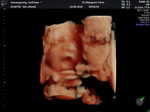

อยากถามแม่ๆว่าถ้าเราอยากจะซาวด์ดูว่าลูกปรกติครบ32มั้ยปากปรกติมั้ยจะซาวด์ได้ตอนอายุครรภ์เท่าไรค่ะต้องบอกหมอมั้ยหรือรออายุครรภ์ถึงหมอจะซาวด์ให้เองคะขอบคุณล่วงหน้าค่ะ